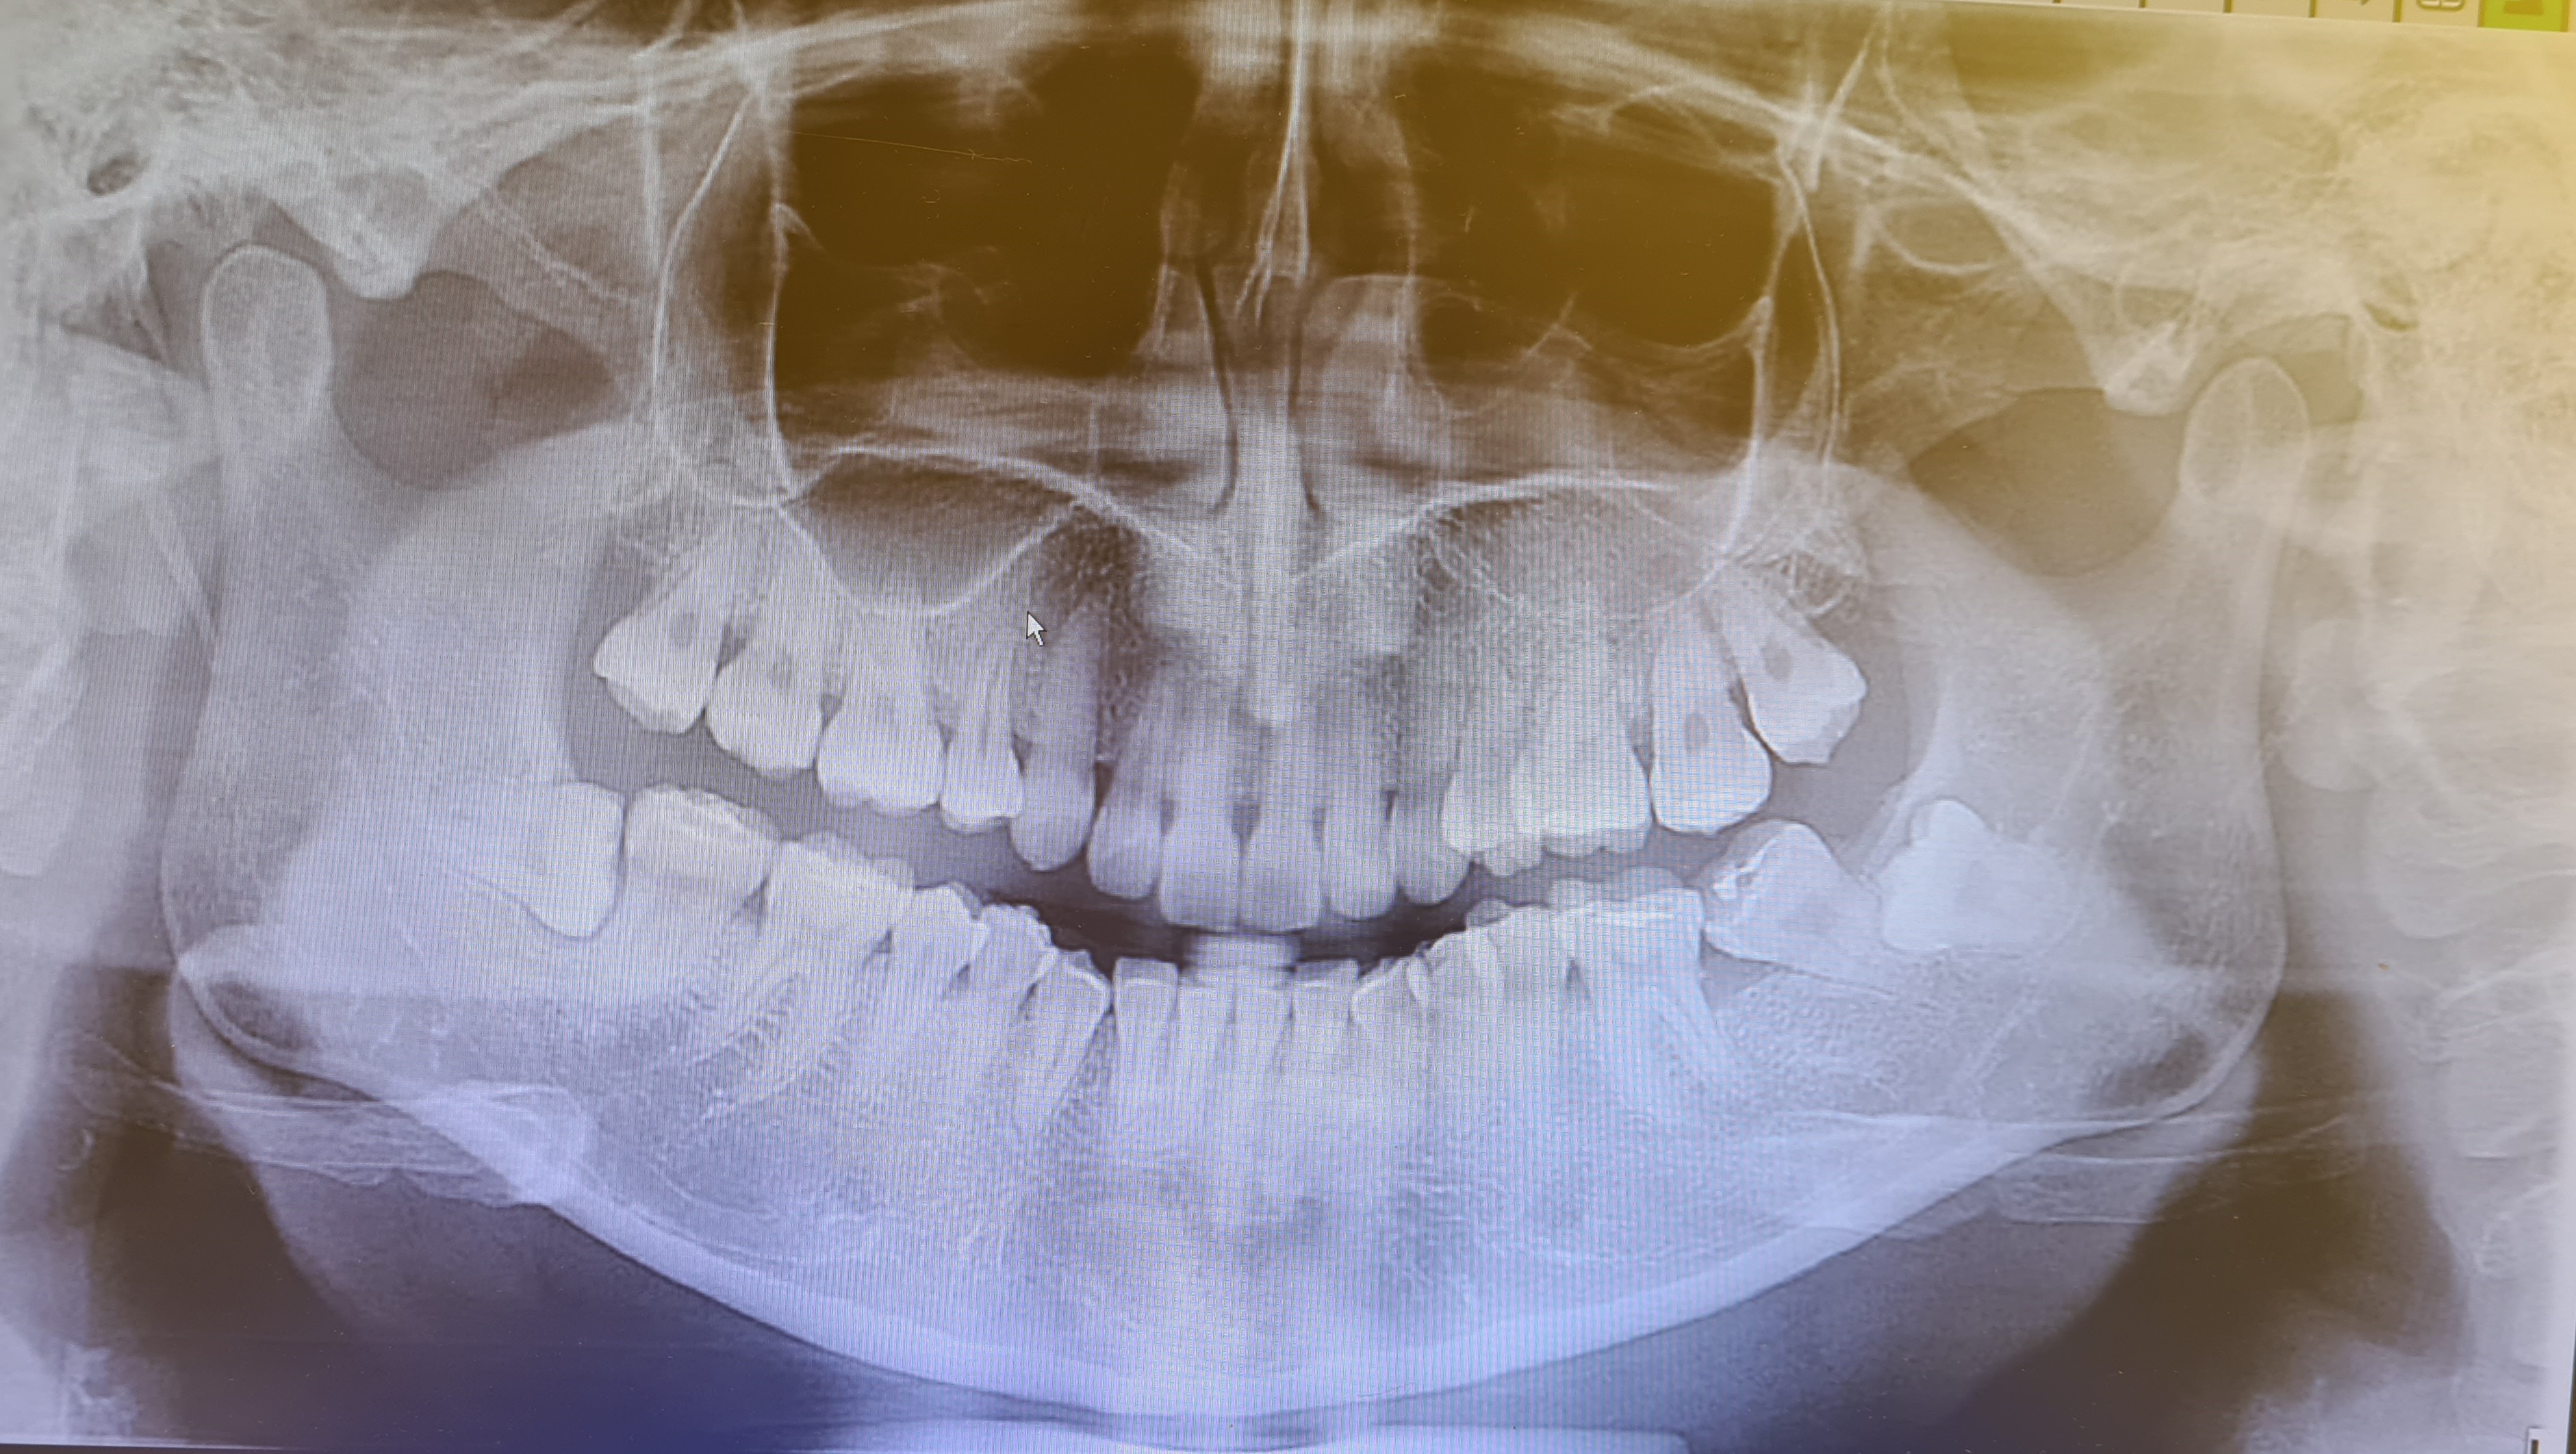

A dicembre mi sono recata dal mio dentista di fiducia per un terribile mal di denti